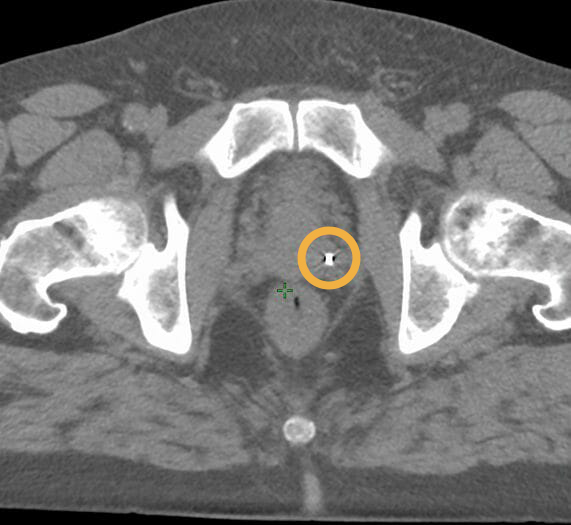

Images showing 0.4×10 mm Gold Anchor MR+ markers, implanted with a ball shape in prostate. Images courtesy of Centralsjukhuset Karlstad.

T2-weighted MRI